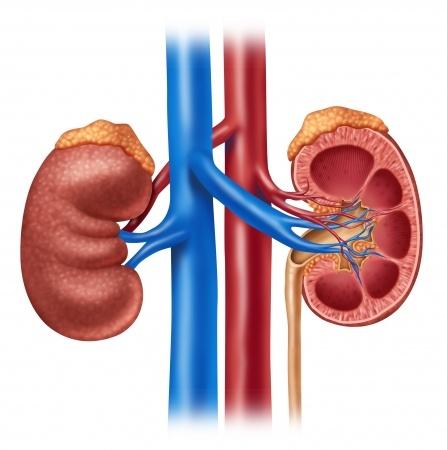

Az ilyen feleslegben bevitt fehérjék károsítják a veséket, drágák és lebomlásuk során cukrok képződnek belőlük. Drága módja a cukor pótlásnak a fehérje fogyasztás.

A húsok kéntartalmú aminosavakban igen gazdagok. Ezek az aminosavak létfontosak, de ha több van belőlük, akkor a szervezetünk lebontja ezeket. Első lépésben kénsav keletkezik belőlük, amik az anyagcsere folyamatok során gyorsan gyengébb savakra "cserélődnek" és a felesleges savak a vizelettel kiürülnek a szervezetünkből. Igen ám, de a vizelet savanyítása azzal a következménnyel jár, hogy megnő a kalcium kiválasztás is a vizeletben, ami a kalcium tartalmú vesekövesség kialakulására hajlamosít. A vesekövek több mint 80%-a a kalcium valamilyen sója.

Ha ezt el akarjuk kerülni, akkor csökkentenünk kell a húsfélék fogyasztást. A felnőtt ember napi fehérje igénye testsúly kilogrammonként 0,6-0,8g. Tehát egy 10 dkg-os hússzelettel bőven fedeztük napi fehérje igényünket.